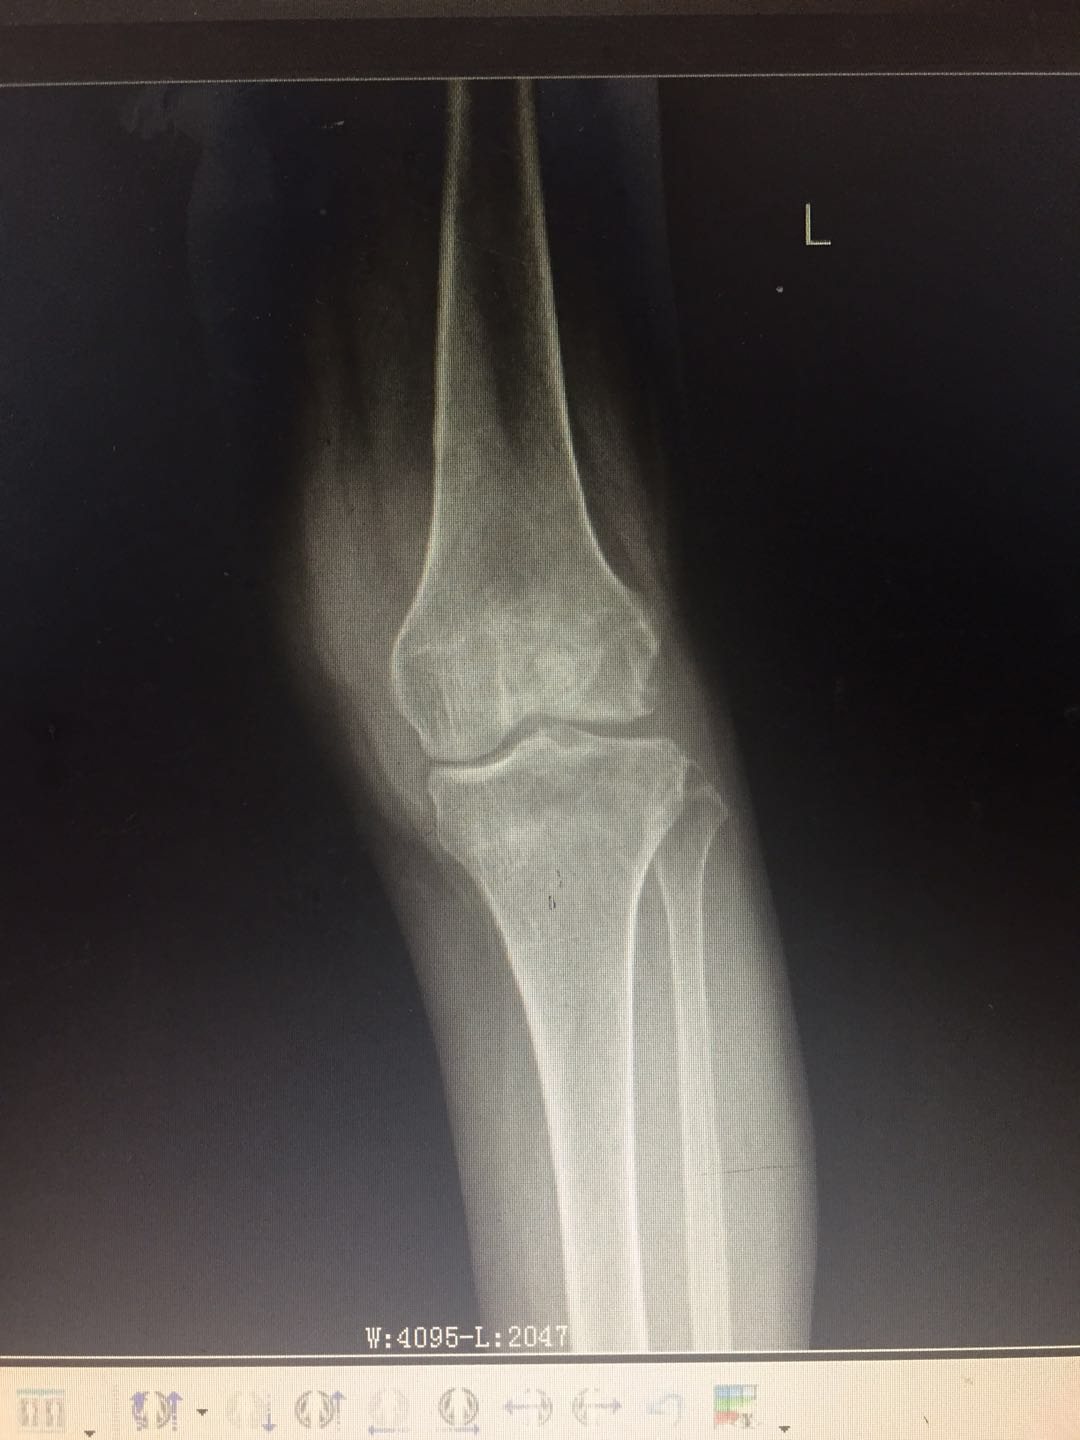

患   者:曾某某 ,女,69岁。

主   诉:左膝疼痛、肿胀、活动受限2年,加重3月,入院治疗。

既往史:2018年6月诊断为“左膝滑膜炎并关节积液”,予关节腔穿刺、理疗、药物治疗后病情好转。无明显潮热、盗汗。

专科检查:左膝部皮温稍增高,皮肤无发红,中度肿胀,呈屈曲位,内侧膝关节间隙处压痛明显,屈伸活动受限,被动活动时疼痛加重,左膝浮髌试验阳性,侧方挤压试验阳性,研磨试验阳性,抽屉试验阴性,肢端觉血运尚可,左下肢肌力感觉未见明显异常。

辅助检查:血沉:37mm/h,C反应蛋白:75.8ng/L,结核杆菌:阴性,降钙素原正常。余检查未见明显异常。

影像资料:

诊        断:

左膝骨性关节炎(K-L分级 4级);

左膝关节滑膜炎并关节积液。